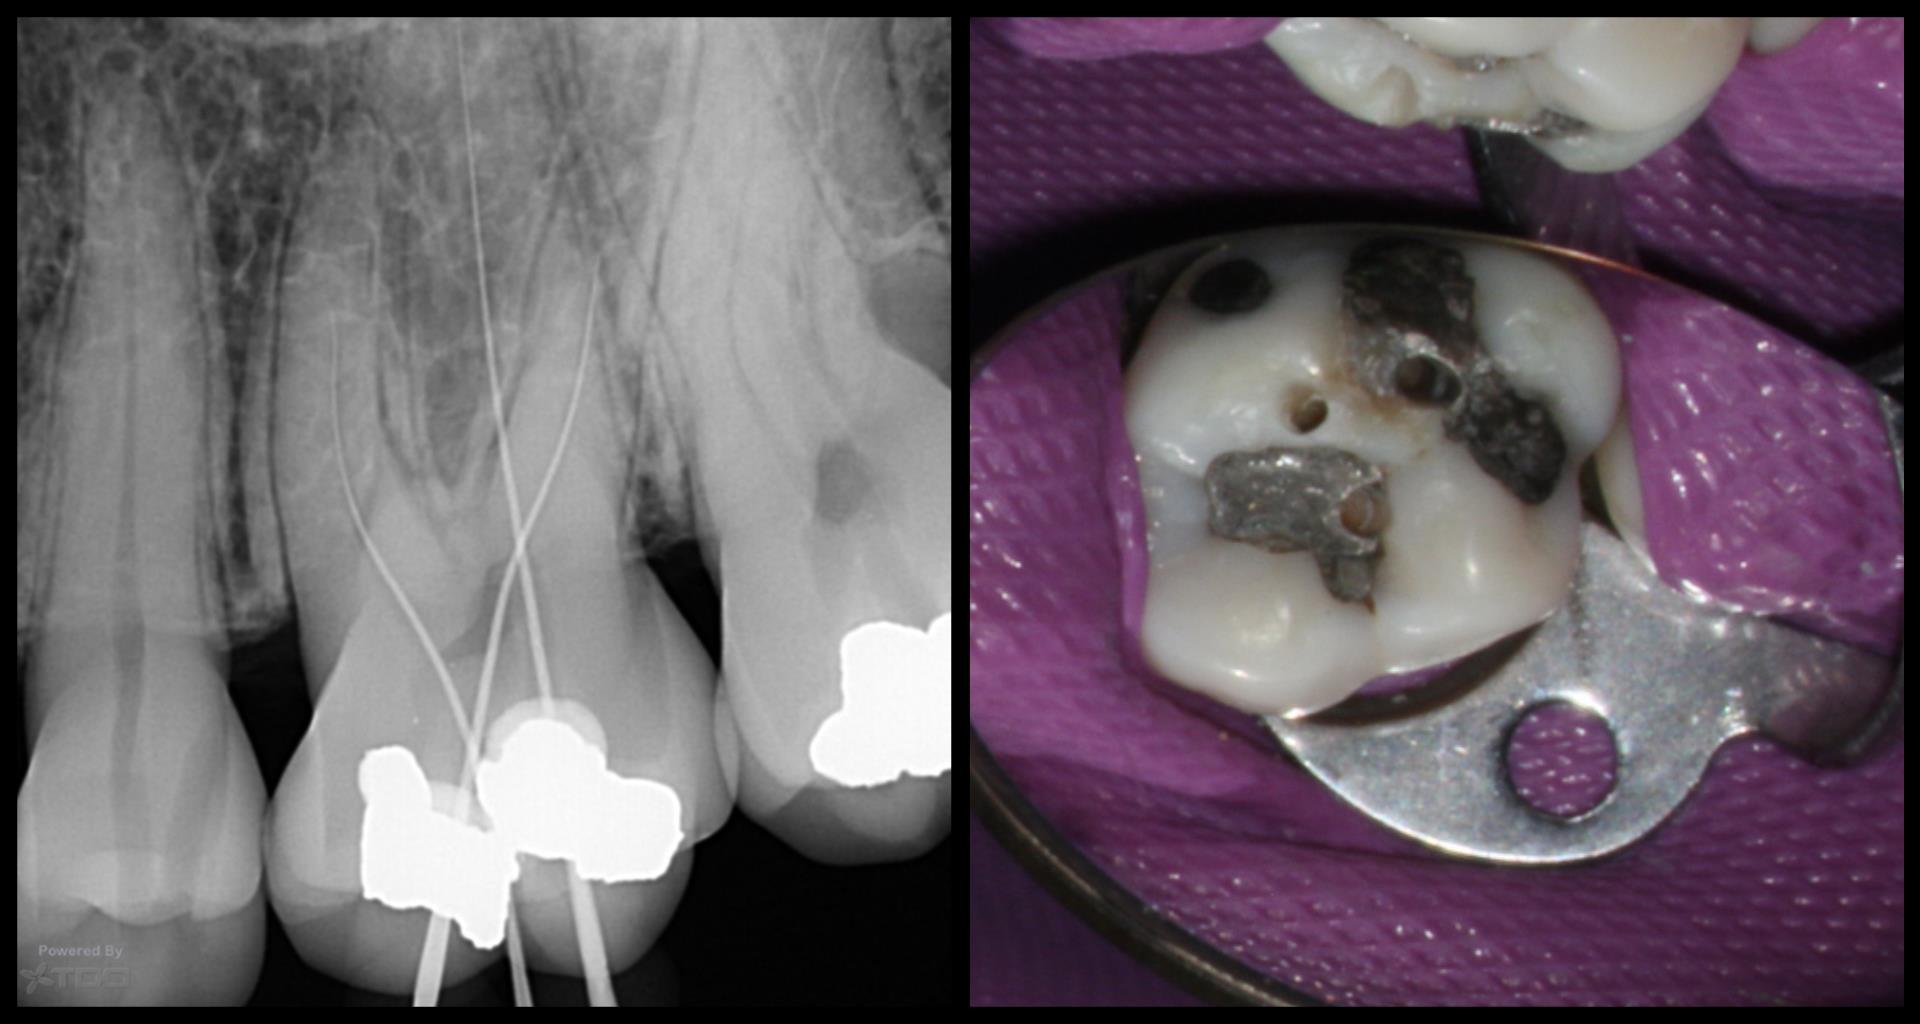

I have always wondered entry into the canal orifice requires precision but even more challenging is to be able to do it through 7-10 mm of dentin.

Any specific bur ? The angles of entry ?

Any slim ultrasonic to smoothen the entry point into dentin and the canal orifice ?

What kind of motions in this access referring to ergonomics ?